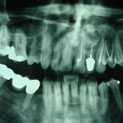

Aunque su estirpe anatomopatológica sea benigna, son quistes que en algunos pacientes provocan grandes destrucciones maxilares, porque crecen de forma asintomática durante años.

Su cirugía es sencilla y está basada en la extracción del quiste con criterios conservadores, y en la reconstrucción del defecto creado por la limpieza quirúrgica.

Para la reconstrucción, aconsejamos hacerlo en la misma intervención y con las bases de ingeniería tisular de la regeneración ósea guiada. Utilizamos como material óseo inductor el fosfato tricálcico tipo beta, mezclado con sangre del paciente y protegido con membrana de regeneración reabsorbible.